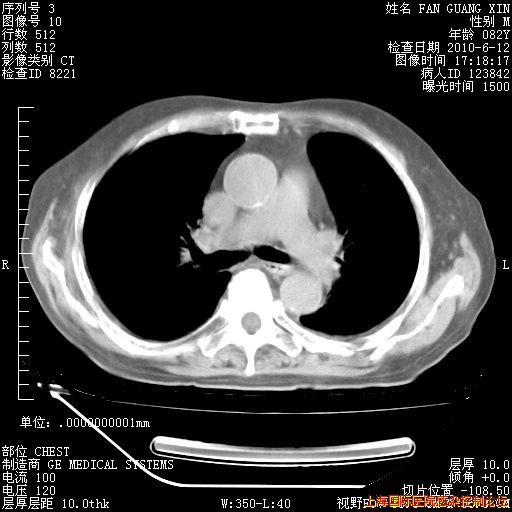

补发6月12日肺部CT肺窗

6月12日肺窗

6月12日纵膈窗